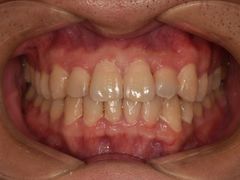

• -德伦口腔

LEE | 19-05-21

报错